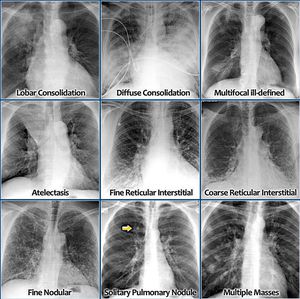

Imp xrays

Xray

Lungs

Pulmonology

Chestxray